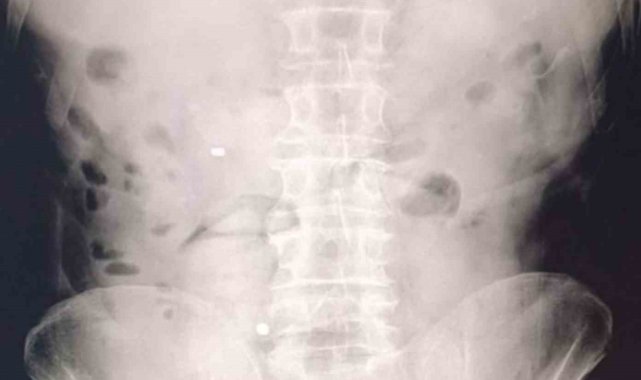

Şüphelilerin hastanede yaptırılan kontrolleri ve çekilen röntgen filmleri sonucunda mide ve bağırsaklarında çok sayıda uyuşturucu madde içeren kapsül bulunduğu tespit edildi. Hastanede kontrollü şekilde gözetim altında tutulan şüphelilerden tıbbi müdahaleler neticesinde toplam 93 parça halinde 1 kilo 70 gram metamfetamin ele geçirildi.

Midelerinden 1 kilo 70 gram metamfetamin çıktı